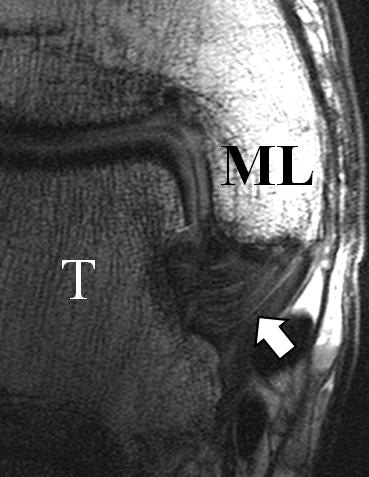

Der Ursprung des Ligamentum fibulocalcaneare liegt unmittelbar kaudal und dorsal des Ursprungs des Ligamentum fibulotalare anterius, so dass gehäuft kombinierte Verletzungen und auch ein gemeinsamer knöcherner Ausriss beobachtet werden. Nach kaudal dorsal verläuft das Band dann nach medial konvex unter die Peroneussehnen. Danach ist ein schräg deszendierender, gestreckter Verlauf bis zum calcanearen Ansatz abgrenzbar (Abb. 10). Dieser zu allen drei Standardebenen schräge Verlauf erschwert häufig die Diagnostik des LFC vor allem bei subtileren Verletzungen. Spezialprojektionen, die dem Bandverlauf orthograd folgen (entweder schräg coronar oder schräg sagittal) erleichtern auch hier die Diagnostik (Abb. 11) insbesondere nicht dislozierter Avulsionen. Assoziierte Verletzungen der Peroneussehnenloge müssen mit beurteilt werden, wobei neben Verletzungen der Sehnen und Sehnenscheiden die Beurteilung des Retinaculum peroneum superius und inferius wichtig ist. In einem Kollektiv von Patienten mit chronischen Außenbandinstabilitäten weisen 50% der Patienten eine Verletzung dieser Strukturen auf 5. Auch hier erleichtern hochauflösende Techniken die Diagnostik (Abb. 12).